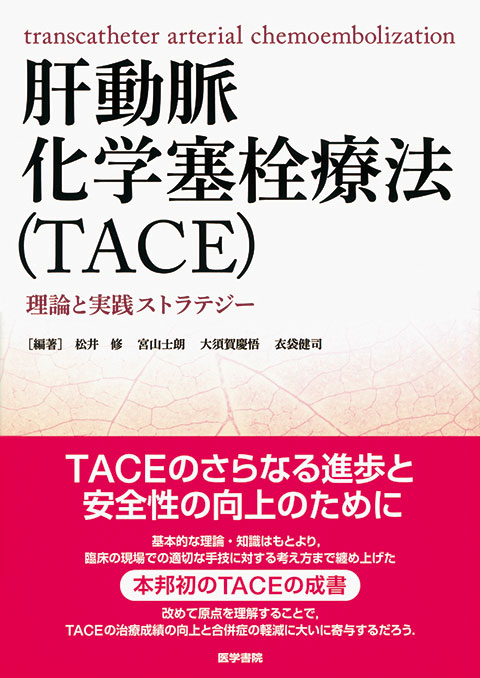

腹部血管画像解剖アトラス | 衣袋 健司 |本 | 通販 | Amazon, 腹部血管画像解剖アトラス | 書籍詳細 | 書籍 | 医学書院,

腹部血管画像解剖アトラス | 書籍詳細 | 書籍 | 医学書院, 腹部血管画像解剖アトラス』 立ち読み,